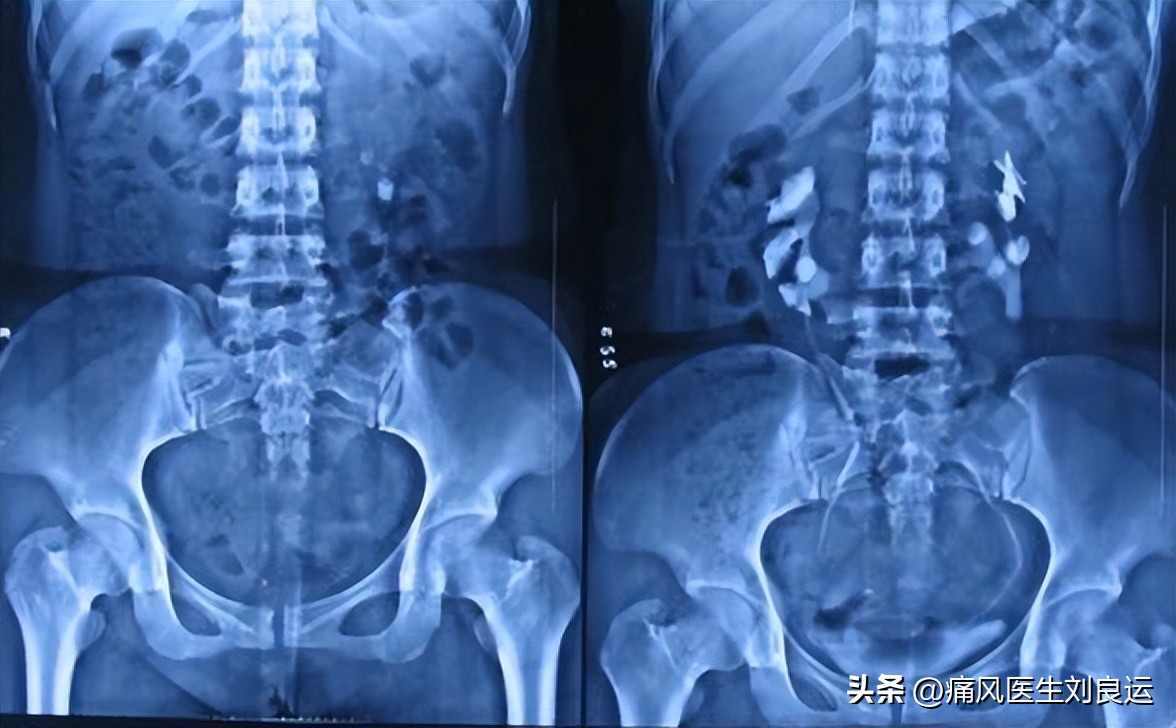

肾脏尿酸盐结晶

痛风可导致尿酸性肾结石